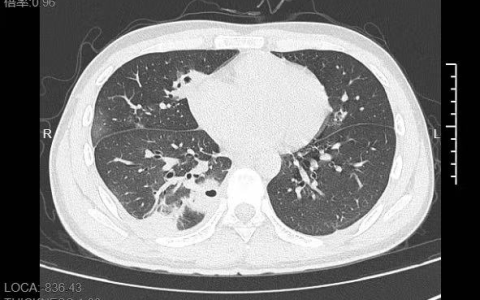

20岁男生挤了颗脸上的痘:肺被啃出10多个洞!

快科技11月24日消息,随后挤掉脸上的一颗痘,竟然有如此严重的后果,近日,宁波大学附属第一医院公布了一起相关案例。 据介绍,20岁的小林(化名)是名大二学生,前段时间为了准备考试,…